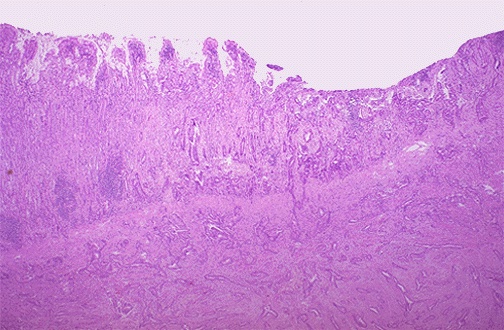

Microscopically, invading adenocarcinoma can be seen here. Normal gastric epithelium at the left merges with the carcinoma at the right, and irregular neoplastic glands infiltrate downward into the submucosa.